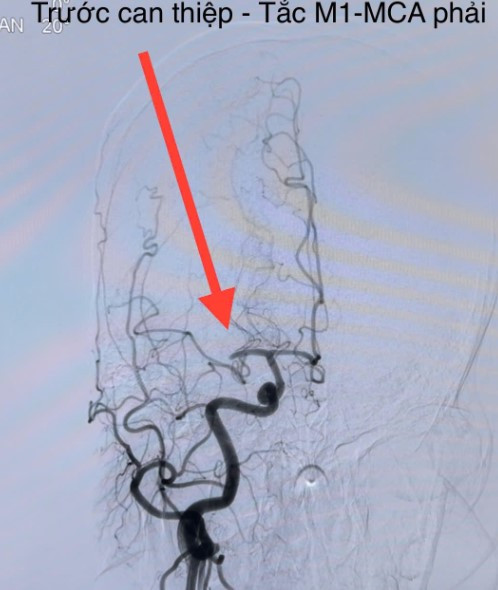

![]() |

| Huyết khối trong mạch não bệnh nhân được lấy ra sau can thiệp - Ảnh bSCC |

Các thủ thuật can thiệp nội mạch: bác sĩ có thể tiến hành lấy huyết khối trực tiếp bằng ống thông hút huyết khối, stent kéo huyết khối trên máy chụp mạch số hoá xoá nền (DSA). Thời gian càng sớm càng tốt, đối với các người bệnh nhồi máu não cấp do tắc động mạch lớn và có thể điều trị trong vòng 24 giờ kể từ thời điểm người bệnh còn bình thường. Từ đó các cục huyết khối sẽ được lấy ra và tái thông mạch máu não cho người bệnh.